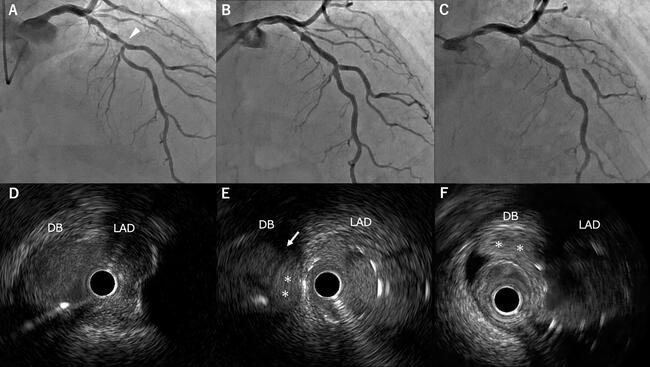

Intravascular Ultrasound-Detected Intimal Flap Predicts Acute Diagonal Branch Occlusion After Drug-Eluting Stent Implantation

Video 1. Post-stent intravascular ultrasound pullback from the LAD showing intimal flap and hematoma at the ostium of diagonal branch. LAD = left anterior descending artery.